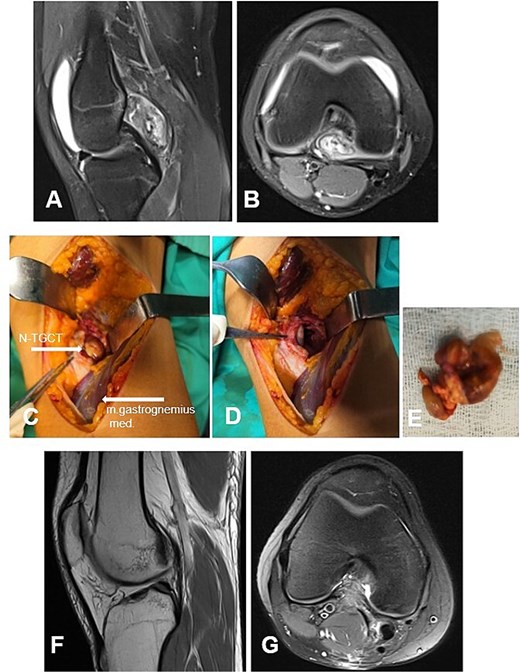

Case 5

А 16-year-old female athlete presented with knee effusion and pain without preceding trauma, persisting for 3 months. Diagnostic MRI revealed an intra-articular, retrocondylar mass with intact cruciate ligaments and menisci (Fig. 6A and B). The lesion was identified as a nodular tenosynovial giant cell tumor and was excised through a posterior partial synovectomy using a medial approach with lateral retraction of the m. gastrocnemius medialis. The tumor was removed sharply and en bloc within macroscopically healthy synovial margins (Fig. 6C–E). At the 12-month postoperative follow-up, the patient was asymptomatic, with no MRI evidence of local recurrence (Fig. 6F and G). Successful return to full athletic activity.

Case 5. (A and B) Preoperative sag and ax MRI TSE PD FS—lobulated edematosus intra-articular neoplasm with a posterior mediocentral localization. (C and D) Posterior synovectomy between m. semitendinosus and m. gastrognemius medialis. (Е) Macroscopic appearance of the N-TGCT measuring 3 × 2 × 2 cm after excision. (F and G) Postoperative 12 m. Sag and Ax MRI TSE PD FS—no evidence of recurrence of the resected neoplasm. PD FS, proton density weighting with fat suppression; TSE, turbo spin echo.